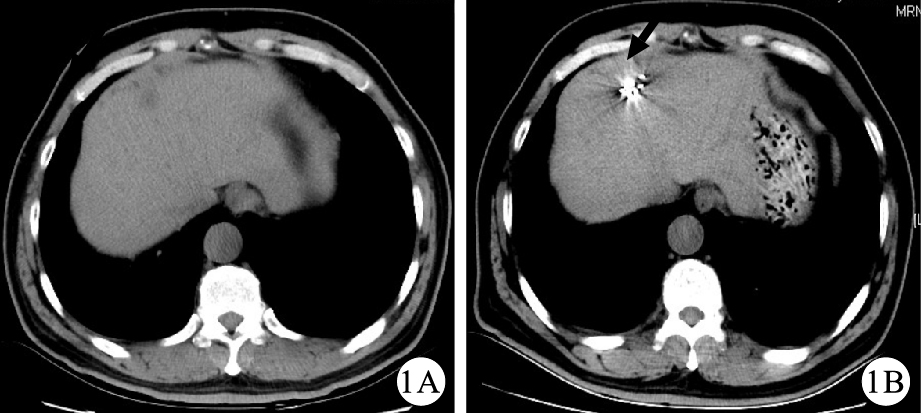

2.2 腫瘤影像學評價結果

本組9例患者行125I放射性粒子植入治療后2個月復查腹部CT,結果顯示,9例患者中,CR占2/9,PR占5/9例,SD占1/9,PD占1/9,總有效者占7/9例,疾病控制者占8/9。具體見表 2。圖 1和圖 2是治療前后典型的腹部CT掃描結果。